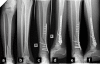

Fracture union was achieved in 34 out of 44 cases (77.3%) (Figures

2 &3). The 10 nonunions were observed in 2 simple closed fractures (1 smoker), in 3 comminuted closed fractures (one smoker), in 2 Grade I open fractures (one smoker), in 2 Grade IIIA open fractures (one smoker) and in one Grade IIIB open fracture (one diabetic). No statistical significant relationship was found between union rate and age (t-test, p

months after fracture. PEMF stimulation of fracture site led to fracture union 5

months thereafter as shown in anteroposterior (c) and lateral ( d) tibial …